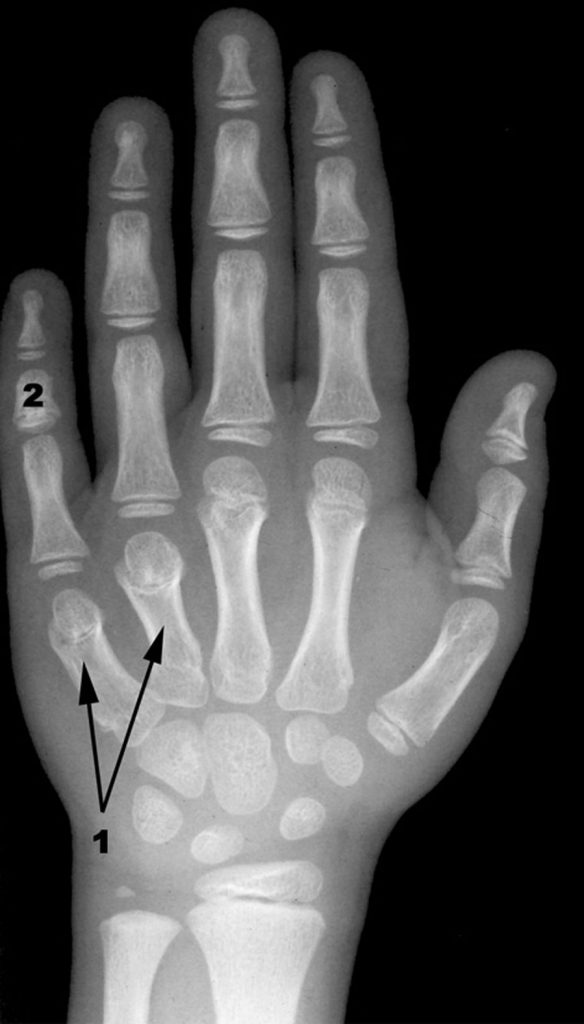

Sur la radiographie de la main, il peut exister un raccourcissement des métacarpiens (en particulier du 4e) (figure 109.2), une ascension du processus styloïde radial, une fermeture de l’angle carpien et une ostéoporose.

Fig. 109.2. Radiographie de la main.

1. Brachymétacarpie des 4e et 5e rayons. 2. Clinodactylie de la 2e phalange du 5e doigt.

Source : CERF, CNEBMN, 2022.